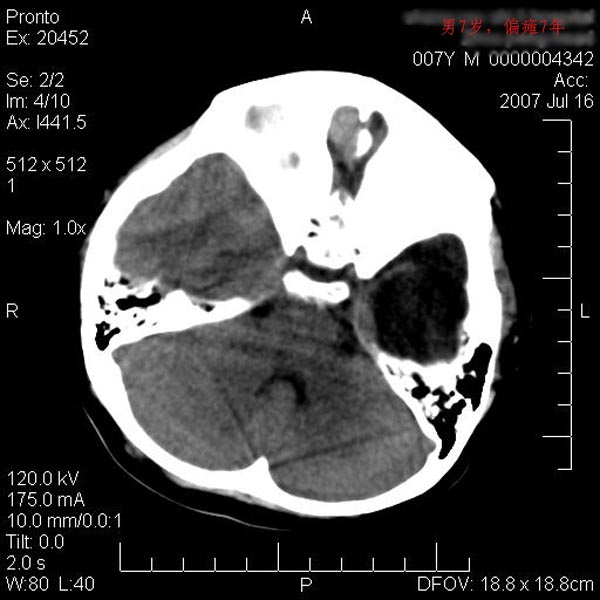

男性 7岁:偏瘫7年,出生时脑内出血。

左侧大脑半球发育不良、软化灶伴穿通畸形形成。

左侧脑叶体积缩小。密度减低,左侧脑室牵拉扩大并向左移位,左侧脑室颞角与侧裂池相通并呈囊性扩张。考虑左侧大脑发育不全,软化灶并穿通畸形。

左侧颅腔变小,左侧大脑半球体积缩小密度减低,呈负占位效应,左侧侧脑室扩大,出生时有脑出血病史。多考虑先天因素,左侧大脑前、中动脉起始部狭窄或闭塞,即烟雾病可能性大。